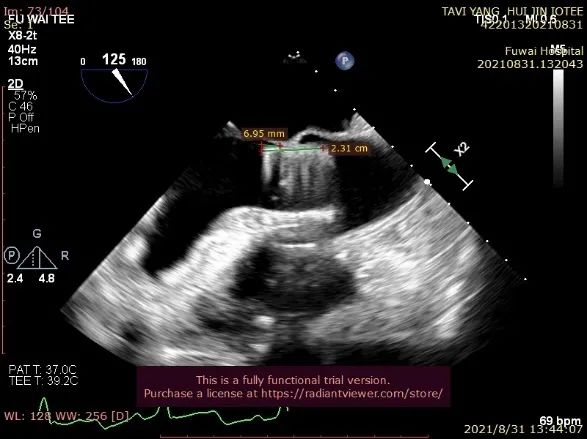

图5. 放射线显示锁丝松开后,输送器逐步回撤,TEE提示人工瓣(导丝处)微量中心性反流信号

术后即刻放射线显示人工瓣膜位置良好,随心跳运动,与周围组织无相对位移;TEE显示人工主动脉瓣金属支架位置良好,瓣环下支架长度约7mm,支架自膨后外径为26.8mm,接近瓣膜真实外径(图6),CDFI多角度观察,舒张期冠脉开口处血流通畅,左室流出道侧人工瓣和自体瓣环之间仅见微量反流信号(图7),收缩期人工瓣口流速良好(峰值流速:2.0m/s,峰值压差:17mmHg)(图8)。

图7. TEE提示做冠脉开口处血流通畅,无冠窦和左冠窦交界处可见微量瓣周漏